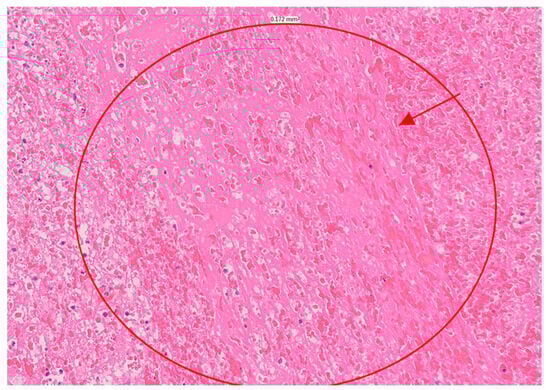

At this point in the patient’s course, the likelihood of infectious endocarditis was considered significant. Blood cultures and serologic markers were drawn, and broad-spectrum antibiotics were initiated. Due to the severity of the MR, which was accompanied by acute heart failure, the patient was referred for urgent surgical intervention and underwent mitral valve replacement within 24 h of her admission. During surgery, two large masses of tissue attached to the posterior annulus of the mitral valve were noticed. The masses appeared to be blocking the valve opening and infiltrating the posterior leaflet, posterior annulus, and surrounding cardiac tissue. The cardiac surgeon noted that the left atrial wall was infiltrated, suggesting a tumor. However, the pathologic evaluation revealed a large, organized thrombus, with no evidence of malignancy (Figure 3). Blood cultures, as well as serological tests for Coxiella burnetii and Bartonella henselae, were negative, as was a pan-bacterial PCR of the surgical sample. Serological tests for antiphospholipid autoantibodies (aPL) were negative, including anticardiolipin antibodies, anti-β2 glycoprotein-1 antibodies as well as a LAC test. Antinuclear antibodies were positive at a titer of 1/640, with a homogeneous and speckled pattern. Anti-dsDNA antibodies were positive at a titer of 1/160, while C3 and C4 were within the normal range.

Figure 3. Histology demonstrated a large organizing thrombus, fibrin and acute inflammation.